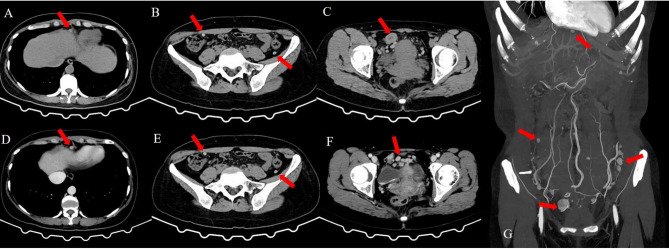

Case presentation: A 41-year-old Chinese woman underwent transabdominal left oophorectomy for a benign SO 18 years prior to presentation in the clinic. She was admitted to our institution for periodic medical examination after ultrasonography revealed a left pelvic mass. The patient underwent total abdominal hysterectomy, right salpingo-oophorectomy, and omentectomy, and multiple biopsies were taken from the omentum and mesentery. Pathology revealed peritoneal strumosis without evidence of malignancy from SO. Afterward, a total thyroidectomy was performed, and a histological examination revealed multinodular goiter. In total, 4400 MBq of 131I was administered, and lesion remission was confirmed. Finally, after 1 year of follow-up, the patient had no evidence of recurrence.